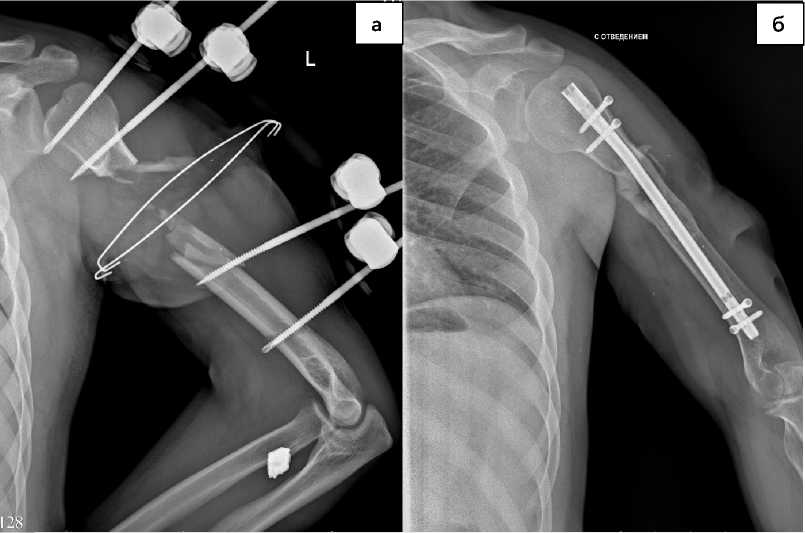

Рисунок 4. Рентгенограммы использования методики последовательного остеосинтеза многооскольчатого перелома верхней трети диафиза левой плечевой кости, а – выполнен стержневой остеосинтез, б – выполнен остеосинтез интрамедуллярным винтом

Figure 4. Radiographs of the use of the method of sequential osteosynthesis of a comminuted fracture of the upper third of the diaphysis of the left humerus, a – rod osteosynthesis was performed, б – osteosynthesis was performed with an intramedullary screw

В большинстве случаев на этапе оказания специализированной помощи использовали последовательное выполнение различных видов остеосинтеза (рис. 3, 4) с сопровождением каждого метода фиксации рентгенографическим исследованием.